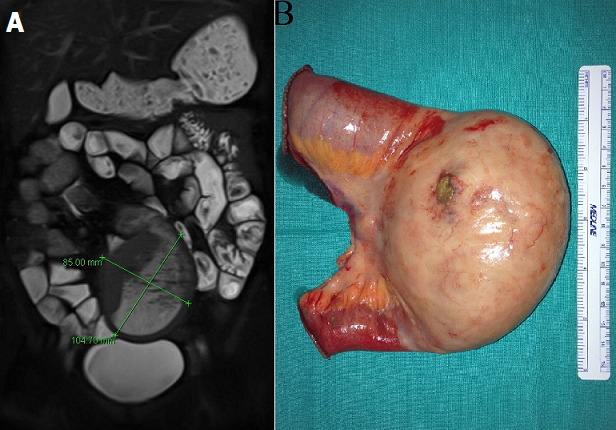

A 45-year-old woman was under study for one year of abdominal pain associated with 4kg weight loss and chronic constipation. An entero magnetic resonance found a mass of 8x10cm on medium ileum suggesting a phytobezoar, with no proximal bowel dilatation. The woman was scheduled for programmed resection. Two weeks after, she presented on our emergency department with an acute abdomen. Exploratory laparotomy showed a bowel perforation of the phytobezoar, and a segmental resection was performed. No more bezoars were found on exploration. She did well after surgery and was discharged home on 6th post-operative day. Pathology revealed a MALT Lymphoma (cells were CD20-positive B-lymphocytes that co-expressed BCL-2 and were negative for CD3, CD5, CD10, CD23, BCL-6 and cyclin D1 on immunohistochemical studies). The overall proliferation index was low with Ki-67 immunoreactivity in approximately 10% of cells. The bone marrow biopsy showed no evidence of involvement by lymphoma. The patient started therapy with rituximab infusions (monoclonal antibody against CD20). In two years follow up she remains asymptomatic and without recurrence. Primary ileal MALT lymphoma is rare, and has not been associated with a specific infectious disease. Bezoar is an unusual cause of small bowel obstruction accounting for 0.4-4% of all mechanical bowel obstruction. The common site of obstruction is terminal ileum. We believe that the primary MALT lymphoma caused a small mechanic obstacle that made alimentary fibers to accumulate and cause the phytobezoar. The perforation required a segmental resection, which finally led to the diagnostic of the MALT lymphoma.